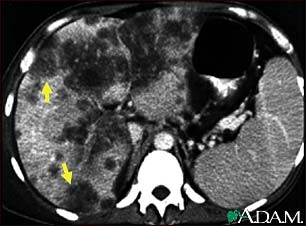

Hepatocellular cancer, CT scan

A CT scan of the upper abdomen showing a widespread (disseminated) carcinoma of the liver (hepato cellular carcinoma). The liver is the large organ on the left side of the picture. Note the moth-eaten appearance.